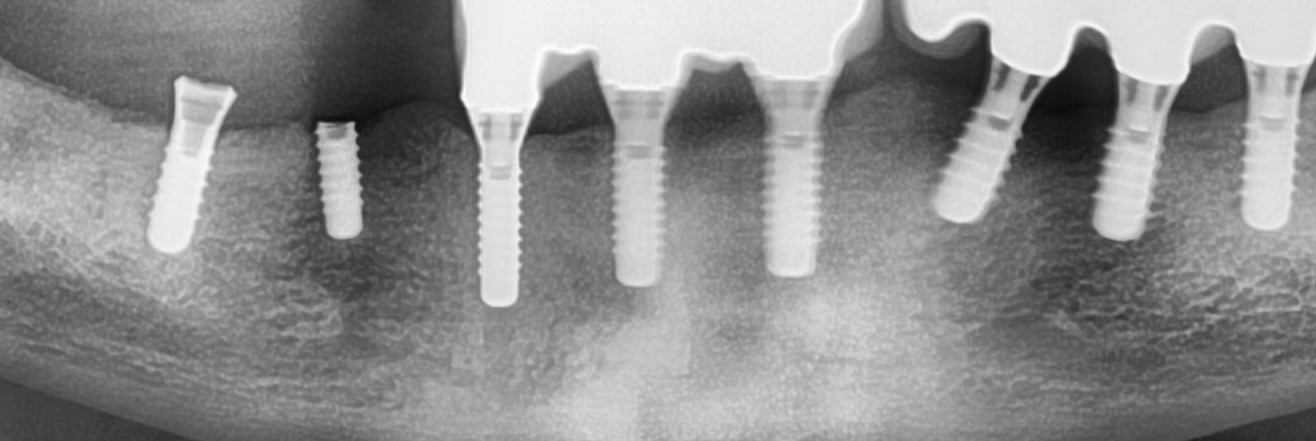

Bij het vast draaien van de boutjes van een brugvan 3 kiezen op 2 implantaten werd ( te ! ) veel kracht gezet en brak van een implantaat het bovenste deel af en het andere (achterste) bovenste deel vertoonde scheurtjes.

De (Straumann) implantaten zijn geïmplanteerd in 2003 en de 3 bruggen in 2018 (met bijplaatsen van 3 implantaten).

De implantaten zitten goed in het bot en de breuk zit gelijk met bovenkant bot.